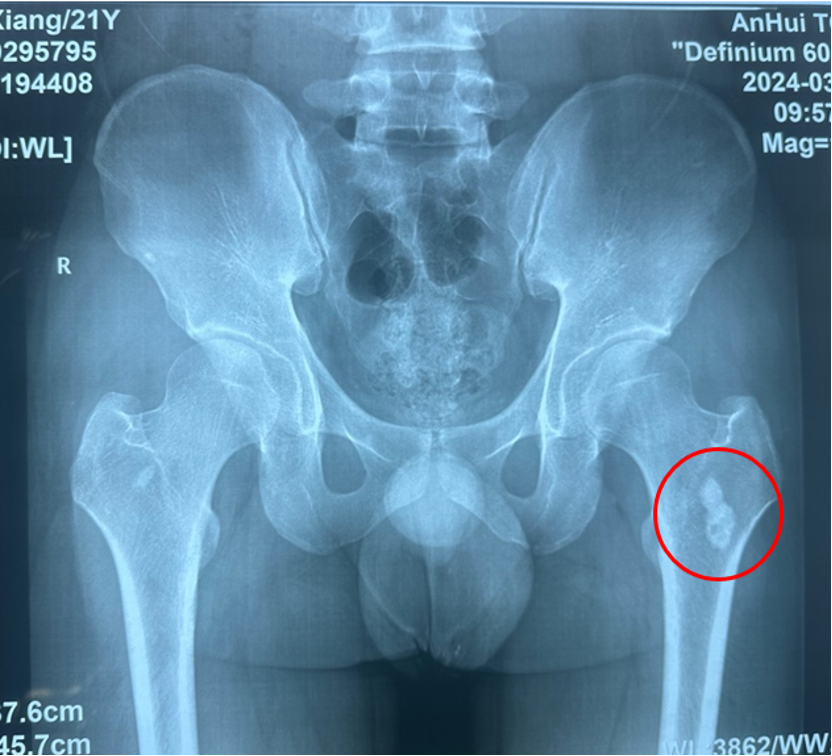

图1:股骨X线可见左侧股骨瘤巢形成及炎性成骨

男性,20岁,因“左侧髋部疼痛不适一年余”就诊,一年前因入校军训后开始出现间歇性疼痛不适,夜间疼痛明显,口服止痛药物可以缓解,一年来逐渐加重,不敢患侧用力,不能进行体育活动,患者下肢出现肌肉萎缩。于外地多家医院就诊,行股骨X线、CT及MRI检查,诊断为“筋膜炎”、股骨骨岛、“骨样骨瘤可能”,无法确诊,患者日常生活困扰较大,后于我院就诊。

入院后诊断为中心型股骨髓腔骨样骨瘤,本型临床症状不如皮质型明显,部分患者疼痛隐匿,单纯射频消融效果较好。入院后第二天全身麻醉后导航下行左侧股骨病灶射频消融术,选择消融针尺寸为15毫米,消融时间11分30秒。术后第二天患者自诉原有疼痛不适症状缓解90%。术后复查MRI可见骨内明显的椭圆形消融范围,精准对应了23*19毫米的消融范围。